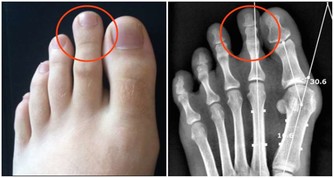

靜脈曲張

靜脈曲張是指由於血液淤滯、靜脈管壁薄弱等因素,導致的靜脈迂曲、擴張。靜脈曲張的外在表現就是青筋暴起,並且長時間消退不了。靜脈曲張雖然聽起來可怕,但是人體並沒有其他不適,似乎不會影響正常生活,所以很多人並不重視。

其實這是非常錯誤的看法,靜脈曲張本身可能是其他病變的繼發表現,如靜脈閉塞。靜脈閉塞對身體的傷害可謂是致命性的,其對心臟的傷害可想而知